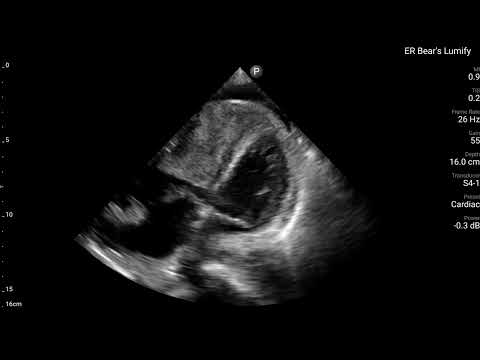

當時,在Bedside也有幫病患做echo。

可以清楚看到RV整團mass lesion,在PLAX打開color flow,在RV也沒有明顯flow。在PSAX view可清楚看到RV dilate with D-sign。A4C view更是清楚看到RV塞滿東西。不管是tumor還是thrombus,基本上已經造成RV strain(RV明顯dilate)。進而看到ECG上面的變化。